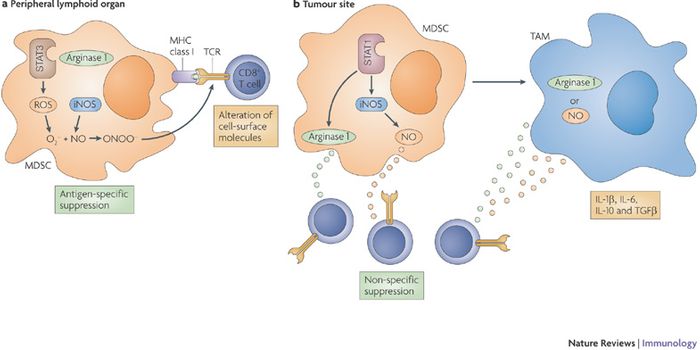

DEC 23, 2015ImmunologyInhibiting large cellular populations of myeloid derived suppressor cells (MDSCs – look up) could be a new therapy ...